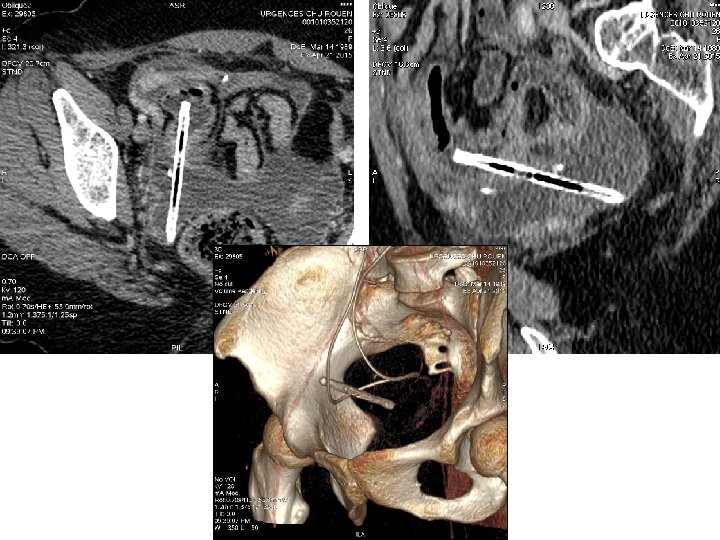

Peut on identifier le corps étranger?

« Un petit dernier… »

« Un petit dernier… » Abcès hépatique sur perforation du 2ème duodénum par une arête de poisson (fête du hareng à Dieppe)